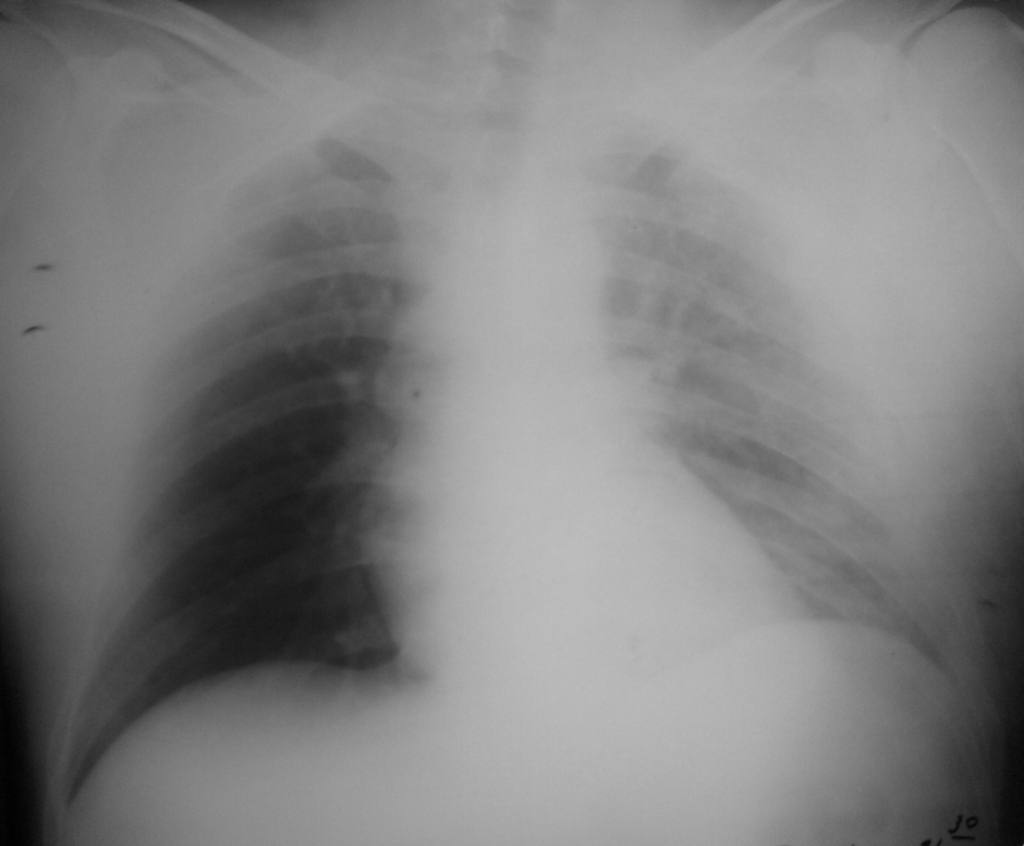

ДТП. Травма грудной клетки.

Вчера поступил мужчина 33 лет, был за рулем. Боли слева. Прошу прощения за каКчество снимков, первый в операционной, второй в отделении на месте через 5 часов, оба лежа. В операционной плевральная пункция, эвакуировано 500 мл воздуха и около 100 мл крови, поставлен дренаж по Бюлау. За прошедшие сутки по дренажу ничего, слева не выслушивается дыхание в нижних отделах + тупой перкуторный звук.

.... снимок после суток бы глянуть... возможно кровотечение продолжается... а на котором через 5 часов...похоже остался пневмроторакс....

Всё ясно и понятно:переломы ребер слева,гемоторакс в условиях  растекания. Мне кажется что и лопатка слева того...

Вижу переломы 3-4-5 ребер слева по ППЛ. Снижение прозрачности легочного поля при отсутствии гемо-, пневмо-   -  ушиб легкого (геморрагическое пропитывание легочной ткани) На втором снимке прямоугольное расширение тени средостения - медиастенит.

Я описала по снимкам перелом четырех ребер слева, гидропневмоторакс. На контроле мне показалось, что легкое расправлено.

Грудина, ребра слева со 2-го по 7-е, альвеолярное кровоизлияние - ушиб верхней доли левого легкого, свободный гемоторакс (около 1200 мл), передний малый осумкованный пневмоторакс - два даже (по типу оставшейся полости?), подкожная и межмышечная эмфизема. Единственное, что вызвало недоумение - как конец дренажной трубки оказался у переднего средостения. Не через лёгкое же его ввели... Наверное (моя фантазия), при пункции добавили воздуха, а при удалении воздуха легкое почти полностью расправилось, вот дренаж и "зажало" под междолевой плеврой. Бред?)) Карррроче, он не функционирует, не в жидкости, не в воздухе.